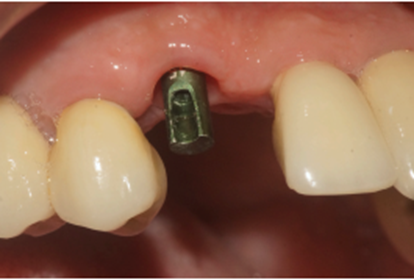

Após 90 dias da instalação do implante, o cicatrizador foi removido e fazendo uso do Kit de Seleção de Componentes da mesma empresa, foi selecionado um pilar Ideale angulado de 3.3 X 4.0 X 1.5 de 17°. Essas mediadas se referem ao diâmetro, altura protética, altura do transmucoso e ao ângulo do pilar, respectivamente (Figuras 9, 10 e 11).

Figura 10 – Pilar angulado sendo selecionado

Figura 11 – Verificando a emergência do parafuso